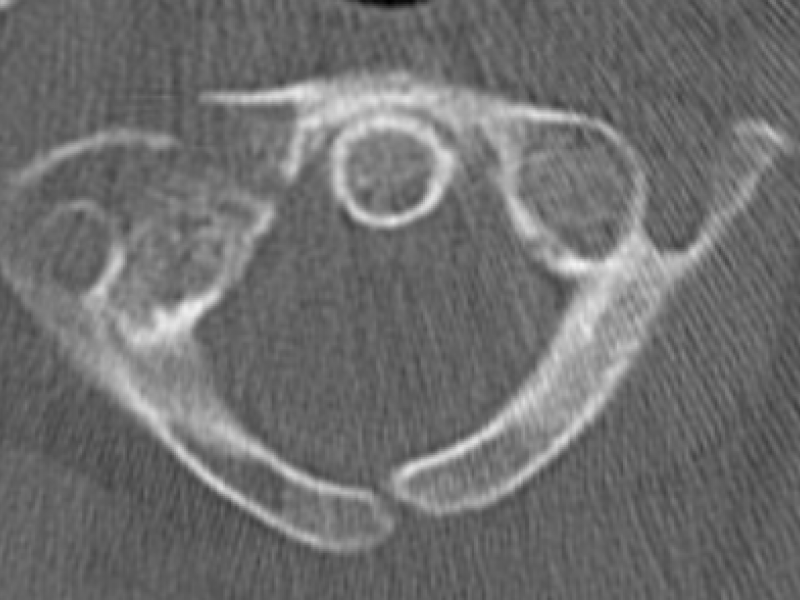

A 61 yo F presents to the ED with neck pain after a fall